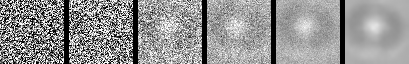

To evaluate the effectiveness of our generative diffusion model in synthesizing realistic SvP images, we first trained separate models for the two most underrepresented particle classes: air bubbles and silicone oil droplets. As described in Section 2.3, each model was trained using only 1,000 real images, carefully excluded from the validation set to avoid data leakage.

In Figure 4(a), we present the training loss for the two diffusion models trained with silicone oil images and air bubble images. Alongside this, Figure 4(b) shows the FID scores computed from 100 generated images at various training epochs (1, 5, 10, 20, 50, 100, 200, 500, 1000). As can be seen, although the training loss plateaus around 0.2, the FID continues to improve over time, indicating that the perceptual quality of the generated samples keeps increasing even after the loss converges. This discrepancy suggests that traditional loss values may not fully reflect improvements in sample fidelity, whereas FID provides a more informative measure of generative quality, particularly in capturing subtle visual cues and morphological accuracy relevant to our application. It is important to note, however, that FID values are not inherently meaningful in isolation and should be interpreted relative to the domain: while natural image datasets typically yield lower FID scores, medical and biomedical images – such as our SvP dataset – are expected to produce higher scores [37, 38].

To visualize how this progression manifests in the output quality, we highlight three training epochs in Figure 4(a), from which we sample and present generated images in Figure 4(c) and Figure 4(d). As shown in these figures, early-stage outputs (e.g., epoch 5 or 10) are low-fidelity, often exhibiting incomplete particle shapes, indistinct boundaries, and missing structural features. In contrast, by epoch 50, the models generate more realistic and coherent particle images, capturing essential characteristics such as spherical morphology, texture, and transparency. This visual progression illustrates how the diffusion models incrementally refine their internal representation of sub-visible particle structure as training advances.

Figure 2 provides a visualization of the denoising process in the reverse diffusion trajectory. Starting from pure Gaussian noise, the model progressively refines the image over 1,000 steps in our setup, gradually introducing particle-specific structures in a visually interpretable manner. To illustrate this process, we present six representative images along the trajectory. This progression highlights the ability of the generative model to recover subtle class-specific features, such as the halo effect in air bubbles or the smooth texture in silicone oil droplets, reinforcing confidence in the utility of these samples for downstream classification.